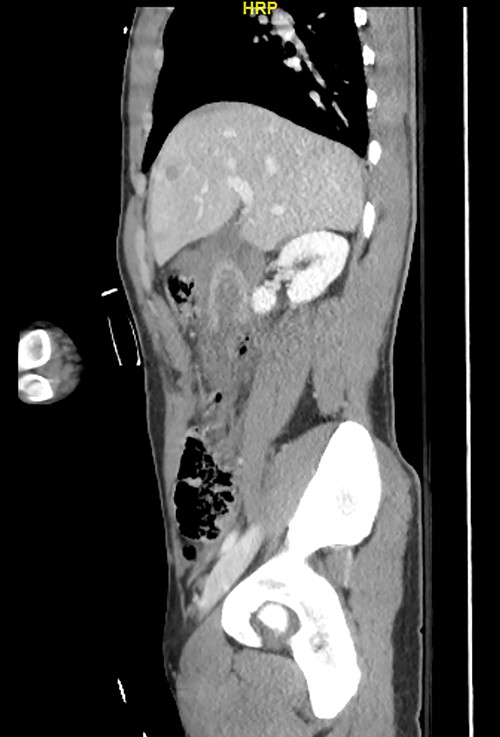

Here, we report a case of a 21-year-old man who was admitted to our hospital following a motor vehicle collision where he was a pedestrian, hit by a car and pushed against the bumper of another car. Upon arrival to the hospital, he was conscious and oriented, with normal vital signs. Abdominal examination revealed ecchymosis over the epigastric area with tenderness, however, no distention was noticed. Focused assessment with sonography for trauma result was positive in the right upper quadrant. His initial blood test results revealed a white blood cell (WBC) count of 26.5 × 109 cells/l and a hemoglobin level of 150 g/l. His serum amylase and lactic acid levels were 92 U/l and 4.53 mmol/l, respectively. His base deficit was 4.3. He underwent abdominal computed tomography (CT) with oral contrast, which showed query duodenal and possible pancreatic transection with active arterial extravasation (Figs 1–3). In addition, CT revealed a comminuted right intertrochanteric femoral fracture without associated vascular injury.

Despite its limitations in distinguishing between duodenal hematoma and duodenal perforation, CT with intravenous and intraluminal contrast remains the gold standard diagnostic test in stable patients with blunt abdominal trauma [1]. In the reported case, CT revealed duodenal and possible pancreatic transection with active arterial extravasation.